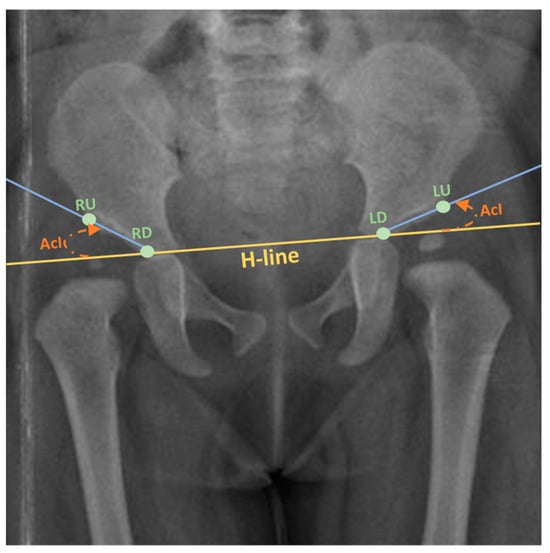

2.1. Data Annotation

3.1. Baseline Landmarks Detection